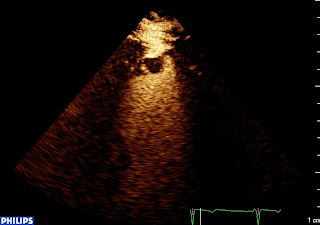

anevrisme apical calcifié from fish Nip echocardiographie on Vimeo.

Et voilà le thrombus! Fini la « maison magique » (que ceux qui ont des enfants en maternelle expliquent aux autres)! Petit, rond, (comme moi), sessile, il apparait en noir, moulé par le contraste, en pleine zone akinétique.